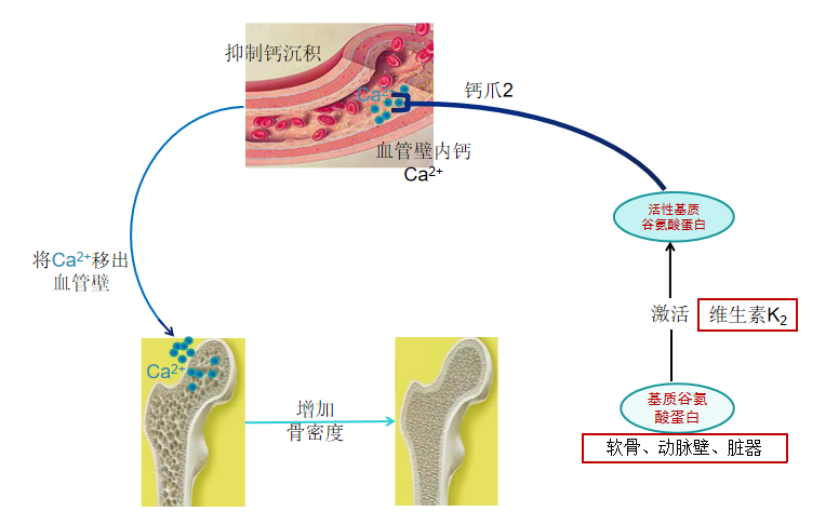

维生素K2激活骨钙素示意图

(3)维生素K2激活骨钙素领钙入骨

维生素K2能激活血液中的骨钙素,撮合骨钙素与离子钙结成终生伴侣,并把离子钙领回家。骨骼才是离子钙的最后归宿,从此离子钙就结束了流浪生涯,改名骨钙,成为骨骼强大的中坚力量。

维生素K2激活骨钙素示意图

(4)维生素K2激活基质谷氨酸蛋白软化血管

基质谷氨酸蛋白分布在软骨、动脉壁和脏器中,能抑制钙离子在这些部位的沉积。

基质谷氨酸蛋白在没有被激活的情况下,也是不具备拒绝钙沉积的作用的。必须在激活状态下才能发挥作用。同样,维生素K2也是基质谷氨酸蛋白的激活剂。维生素K2通过激活基质谷氨酸蛋白对血管壁、软骨和脏器等不该有钙沉积的部位下手,把这些走错了路,认错了门的钙清理出去,并把它们也领回骨骼,从此这些迷失了方向的钙终于脱离了泥潭,回到了骨骼的怀抱。

脱离了钙的纠缠,血管壁焕然一新,恢复了原本应有的韧性和弹性。软骨也恢复了弹力,变得更加光滑,使关节炎得以痊愈。只要身体内维生素K2的量始终保持充足,相信脏器中沉积的钙迟早也会被清理掉的。